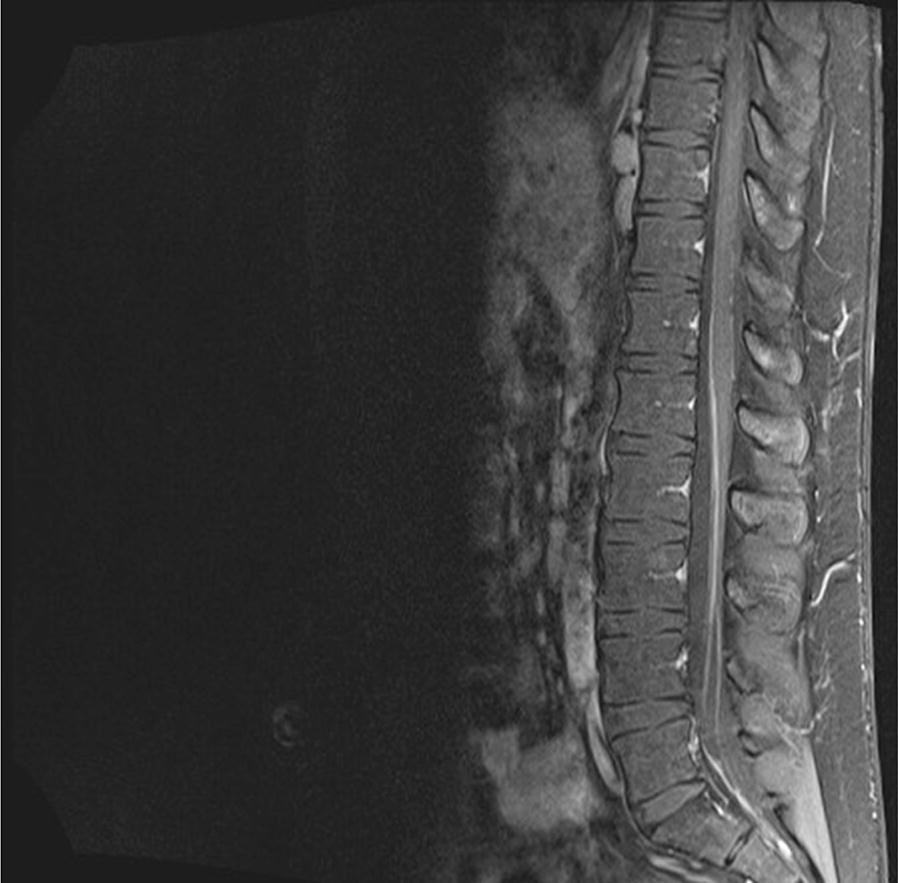

Fig. 2From: The critical role of histology in distinguishing sarcoidosis from common variable immunodeficiency disorder (CVID) in a patient with hypogammaglobulinemiaMRI of the cauda equina. Enhancing lesions of the nerve roots are seen consistent with granulomatous inflammation. A biopsy was not possible, given the locationBack to article page